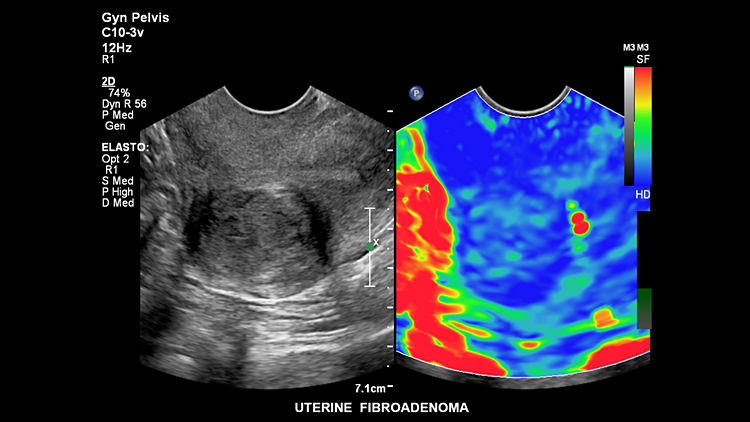

УЗИ аппарат Philips Epiq 7 поддерживает два вида эластографии (компрессионная, со сдвиговой волной). Эти виды визуализации предоставляют достоверные и эффективные результаты исследования жёсткости ткани. Благодаря функции DICOM одновременно просматриваются результаты КТ, МРТ, ангиограммы и прочие ультразвуковые снимки. Технические характеристики оборудования помогают врачу принимать точное и верное решение в процессе интервенционных процедур.

Эластография сдвиговой волной

Опция эластографии с количественным точечным анализом параметров сдвиговой волны позволяет выполнять виртуальную биопсию при использов

Соноэластография

Высокочувствительная визуализация на базе анализа деформации не требует внешней компрессии и позволяет оценивать относительную упругос

Фиброаденома матки, C10-3v

Фиброаденома матки, C10-3v